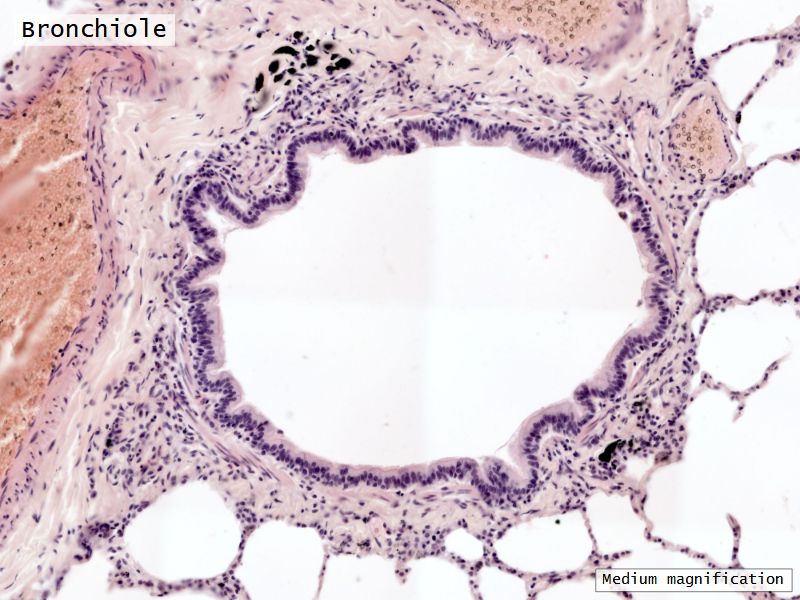

Respiratory epithelium

- Pseudostratified

- Ciliated

- Columnar

- Epithelium with

- 4 Cells

- Ciliated columnar cells

- Non-ciliated columnar cells

- Goblet cells

- Basal cells